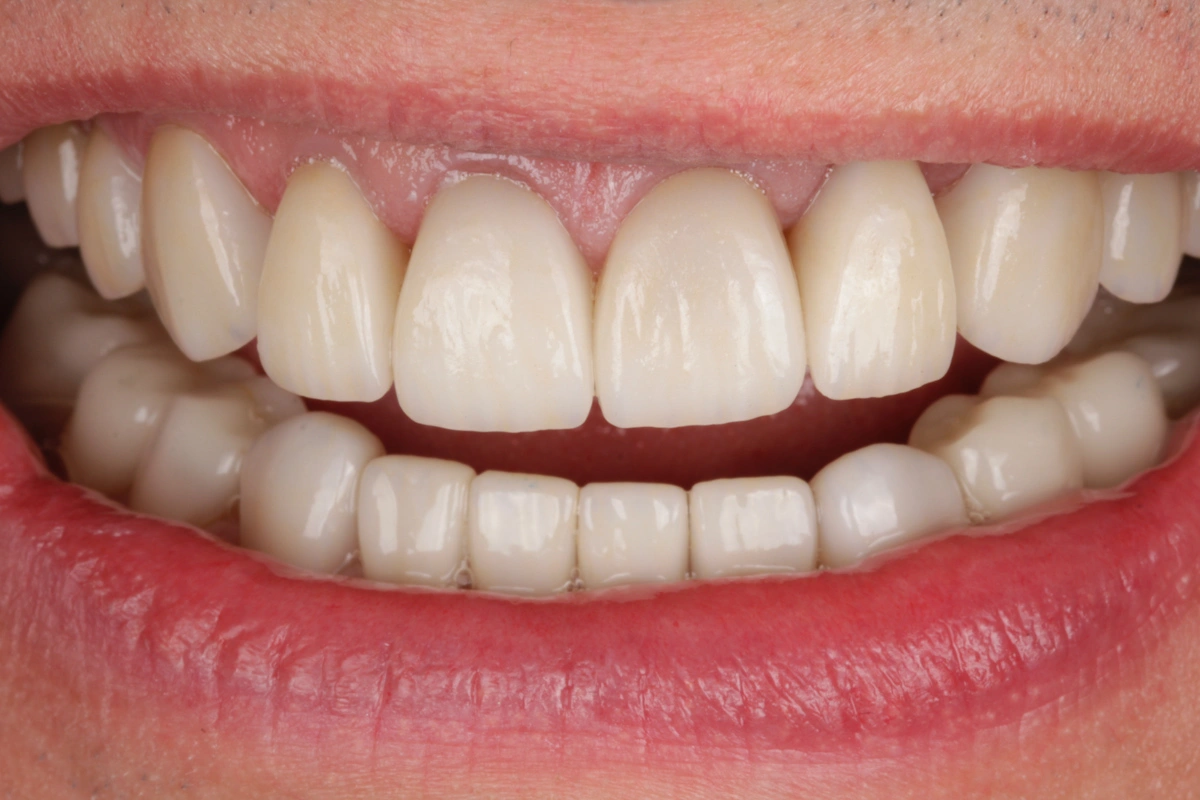

«Rehabilitación completa adhesiva en paciente joven con desgaste dental severo y tinción por tetraciclinas.»

En este caso se trata de un paciente con desgaste dental severo y tinción por tetraciclinas grado IV.

Tras realizar un estudio exhaustivo optamos por una rehabilitación completa con coronas, carillas e incrustaciones en disilicato de litio. Realizamos una prueba previa a la preparación de los dientes para establecer la longitud de los dientes definitivos.